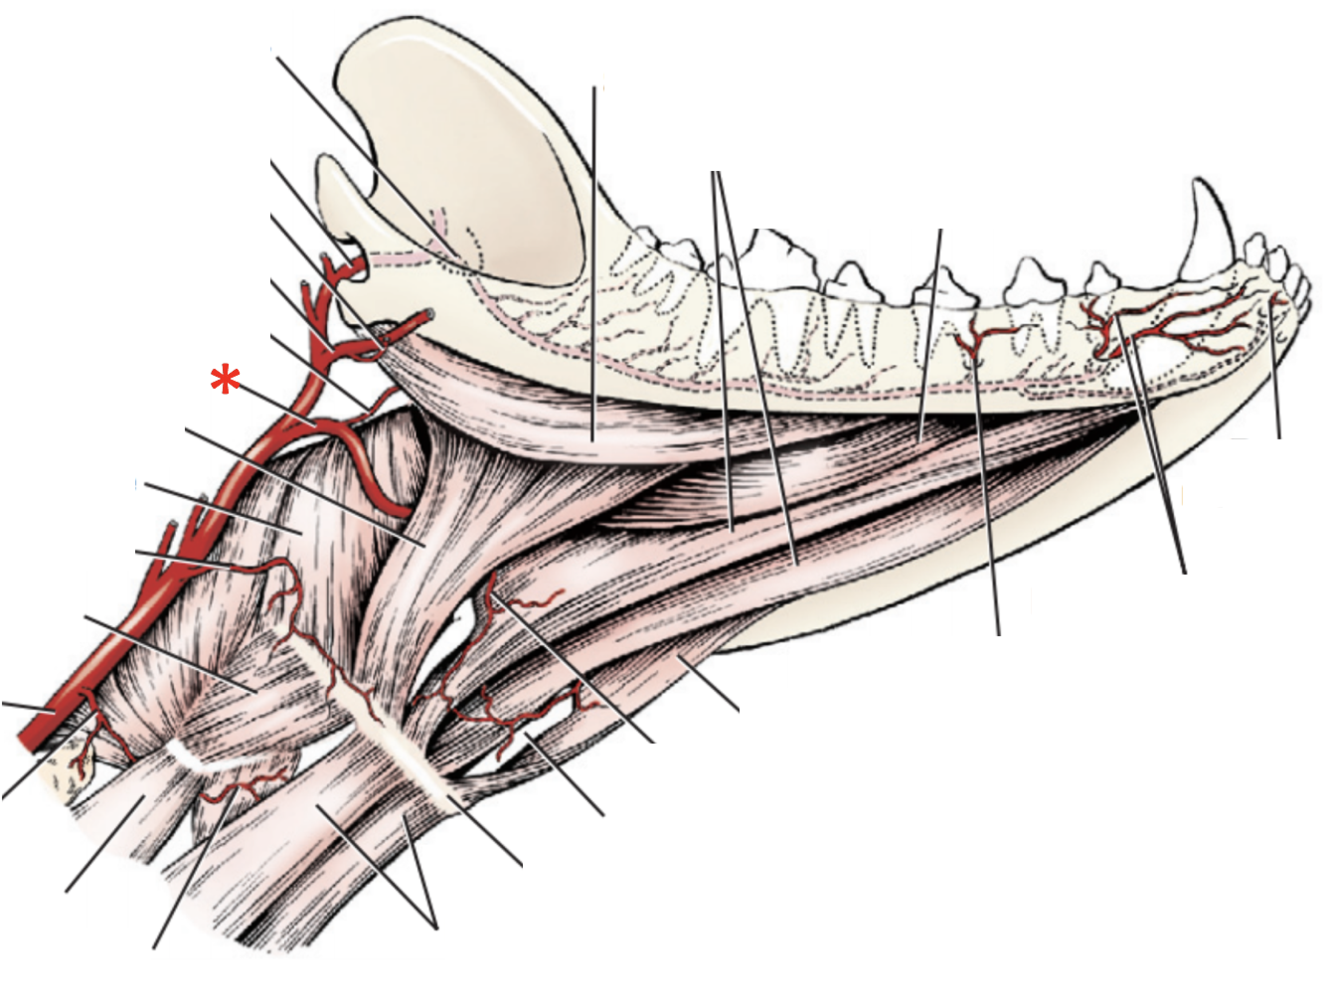

A. lingualis

A. sublingualis

A. lingualis

A. laryngea cranialis

A. laryngea cranialis

A. lingualis

A. facialis

A. sublingualis

**A.** **lingualis**

**A. lingualis**

**A.** **laryngea** **cranialis**

**N.** **laryngeus** **cranialis**

**Tr. vagosympathicus**

**Ggl.** **distale** **of n. vagus**

**Ggl.** **cervicale** **craniale** **of n.** **sympathicus**

**A.** **laryngea** **cranialis**

What can be done to better improve access to *for.* *jugulare* and therefore the vagus group?

Remove:

* *M. digastricus*

* *Lnn. retropharyngei mediales*